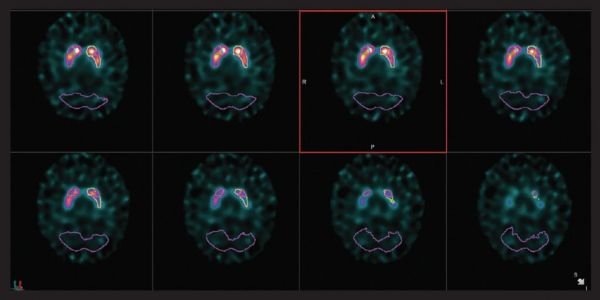

心脏

VERITON ™ 采用我们成熟的CZT探测器技术,可实现更好的协议优化。考虑使用如此处所示的标准剂量的高分辨率2分钟MPI采集,或选择显着更低的剂量同时保持短的采集时间。通过扩展示踪剂使用来检查增加未来心脏实践的方法。